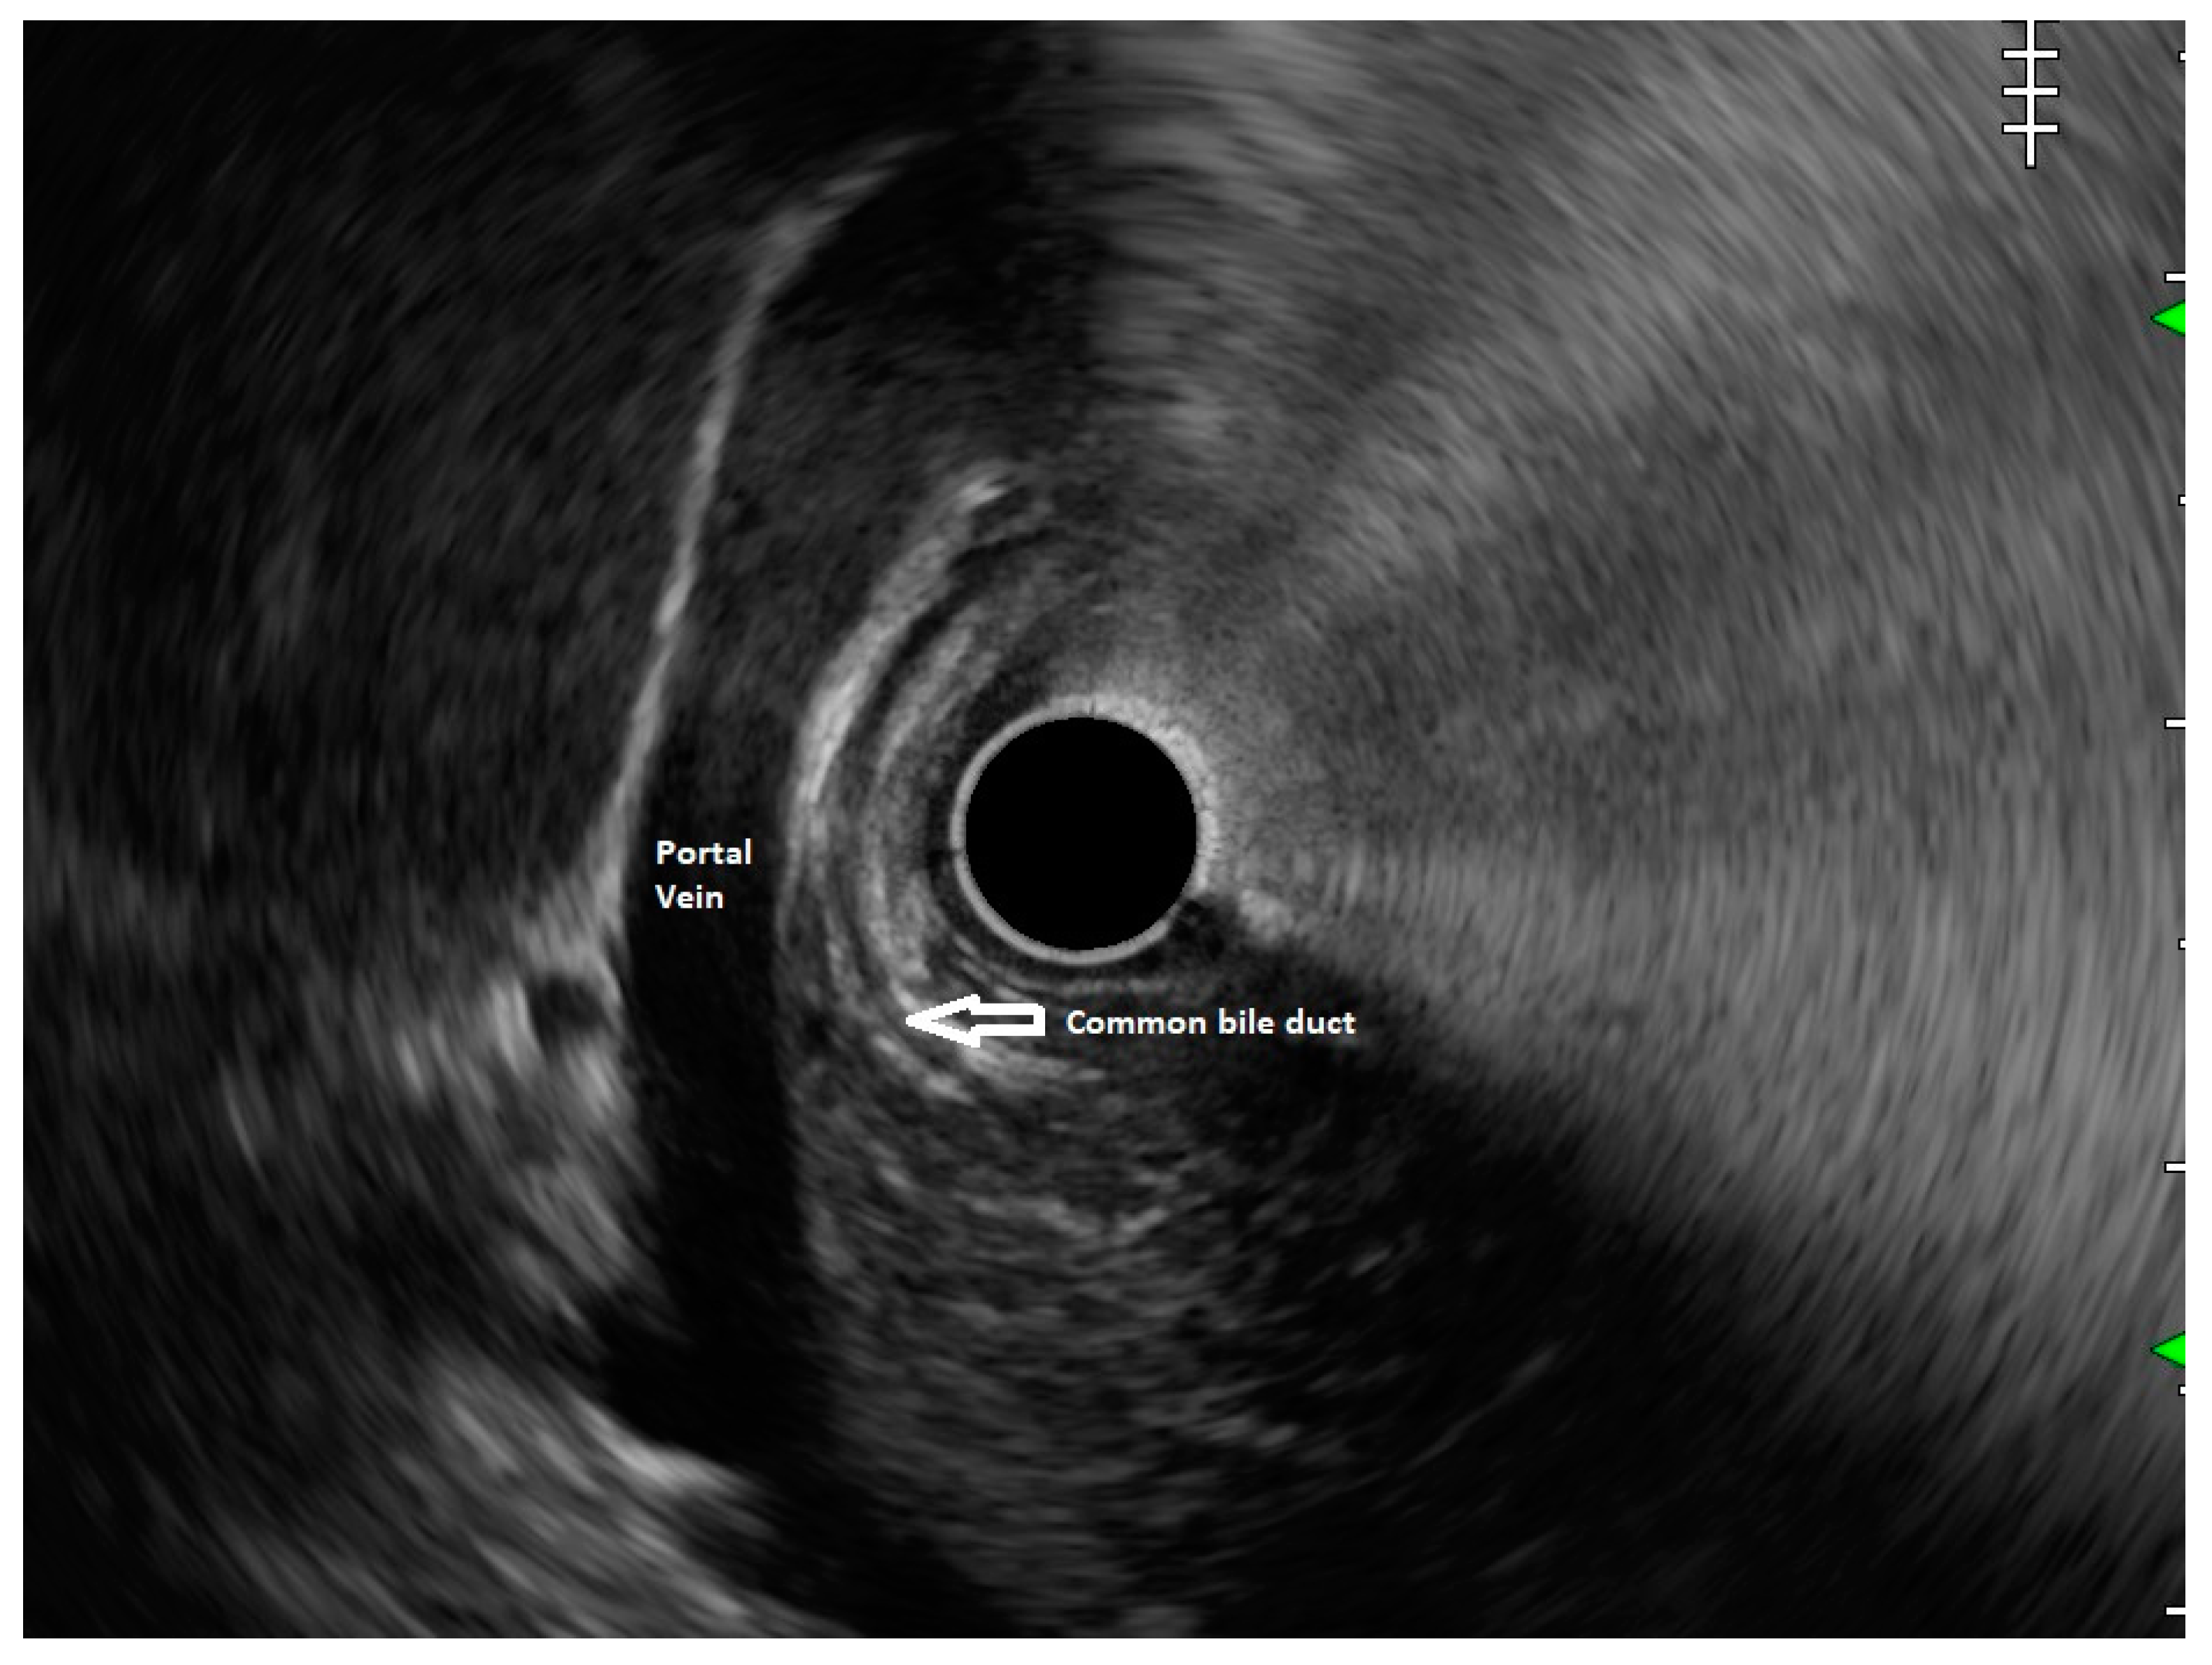

In routine endosonographic examination, all parts of the pancreas are comprehensively examined when seen from three stations, that are the apex of the duodenal bulb, papilla and distal to the papilla. Among these, the best position is the apex of the duodenal bulb as it brings the major portion of the head of pancreas, distal common bile duct and the portal vein in the same frame. For positioning, the EUS scope is advanced along the greater curvature of the stomach and when pylorus is visible, the tip of the scope is negotiated through it followed by air insufflation of the duodenal bulb. This is followed by gentle downward deflection of the tip of the scope making the duodenal bulb visible. Doppler imaging helps differentiating bile duct from the arteries (hepatic artery and the gastroduodenal artery) and portal vein. At this point, the endosonologist gets the view of distal CBD, pancreatic duct, and the portal vein in a single frame in which one structure appears to lie on top of the other and this is called as the ‘stack sign’ (Figure 1) and absence of stack sign suggests possibility of pancreas divisum (Figure 2). As these structures do not lie in the same plane, various manoeuvres like clockwise and counter clockwise rotation and right and left torque are required for a detailed examination of these structures.12 Although this sign is conventionally described in radial EUS, linear EUS can also detect similar anatomical configuration although there are some subtle differences in linear EUS. In linear EUS, usually the ‘stack’ consists of distal CBD and pancreatic duct which are seen on parallel axis (portal vein is not seen). However, superior mesenteric vein (SMV) or artery (SMA) can be seen on linear EUS in a different axis once a clockwise rotation is performed and origin of portal vein from the SMV can also be easily demonstrated (Figure 3).27

Figure 3. Stack sign on Linear EUS.